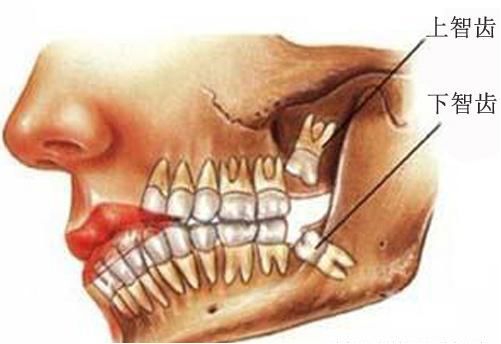

所以拔智齿会损伤神经吗

看下图

如果是处于特殊位置的智齿,还是有可能的

(但概率极低)